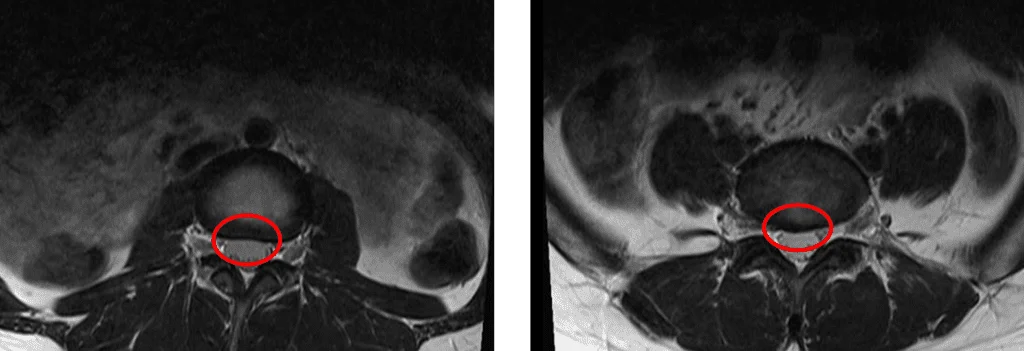

Аксиальная Т2-взвешенная МРТ поясничного отдела позвоночника

При рассмотрении аксильной МРТ видно, что на снимке слева – здоровый межпозвоночный диск, а на снимке справа – диск (L5/S1) выпирает в сторону спинномозгового канала.

Сужение позвоночного канала происходит вследствие дегенерации межпозвоночных дисков.